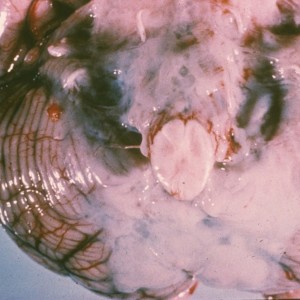

- Causes chorioretinitis (usually bilateral), macrocephaly (due to intrauterine hydrocephalus), seizures, developmental delay, jaundice, hepatosplenomegaly, thrombocytopenia, and purpuric rash.

- MRI with calcifications of the basal ganglia and corticomedullary junction.